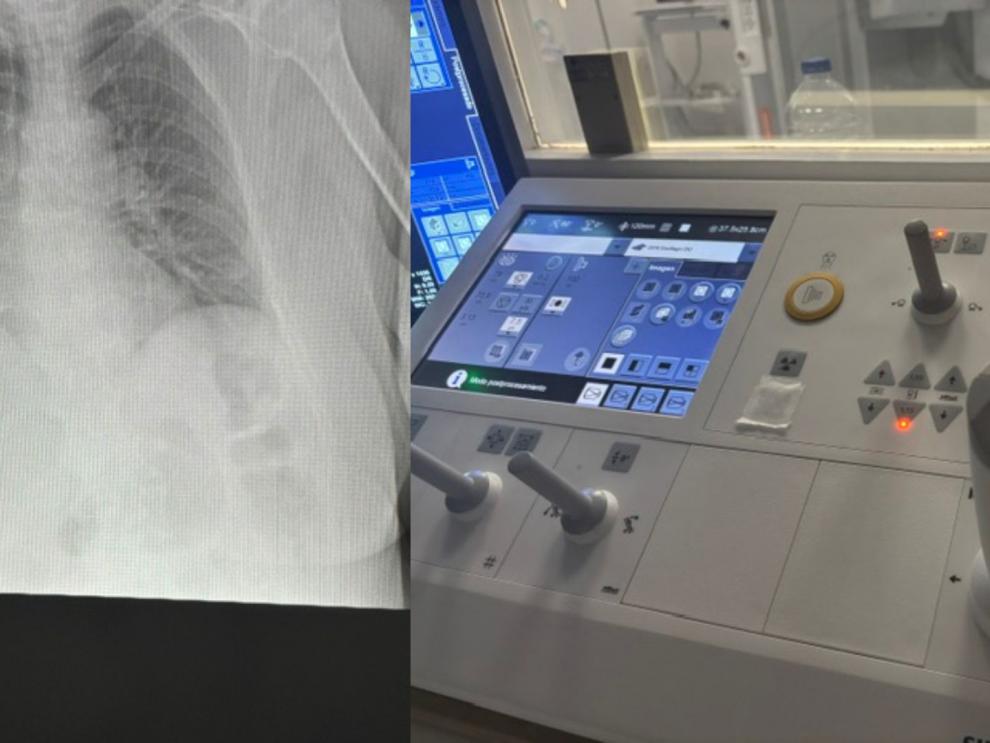

Imagen radiográfica junto al panel de control utilizado por los profesionales para ajustar y supervisar la emisión de rayos X durante la prueba.